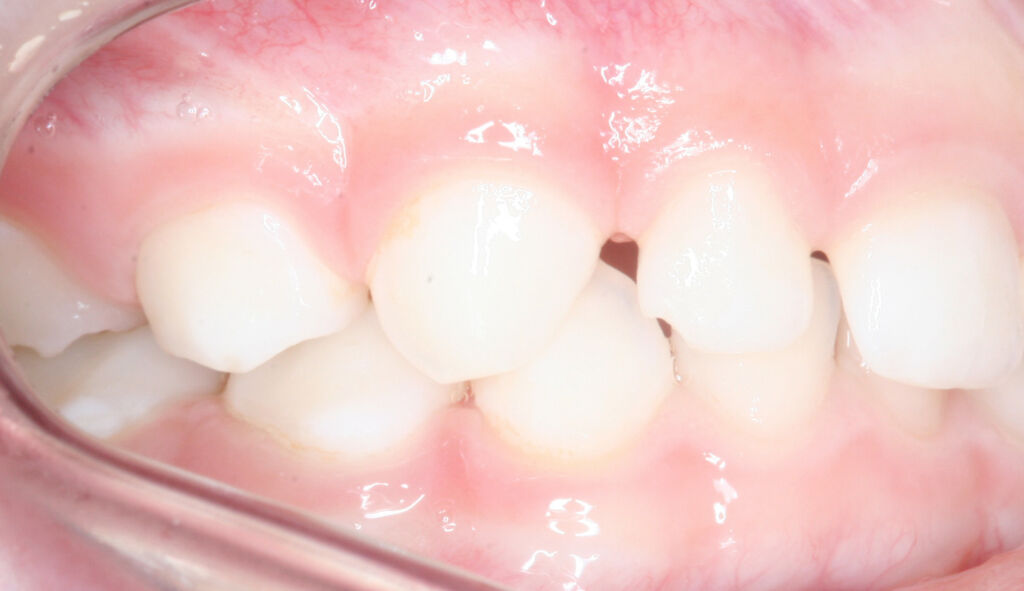

A relação transversa pode ser comparada à relação de tampa-caixa, onde a maxila é a tampa e a mandíbula é a caixa, ou seja, precisamos avaliar a relação de “largura”entre os arcos. Para avaliar a relação transversa é importante observar se os dentes estão verticais em relação a sua base óssea e avaliar a relação de encaixe entre os arcos.

Observe na imagem ao lado, se você observar bem vai perceber que os dentes inferiores estão levemente inclinados para lingual, provavelmente “buscando” uma relação oclusal com uma maxila mais estreita em relação à mandíbula. Não quer dizer que sempre nessas situações clínicas será necessário intervenção, porém, será importante avaliar outros aspectos funcionais para definir se será ou não necessário intervir. Ou seja, este talvez seja o caso de encaminhar para uma avaliação com especialista.